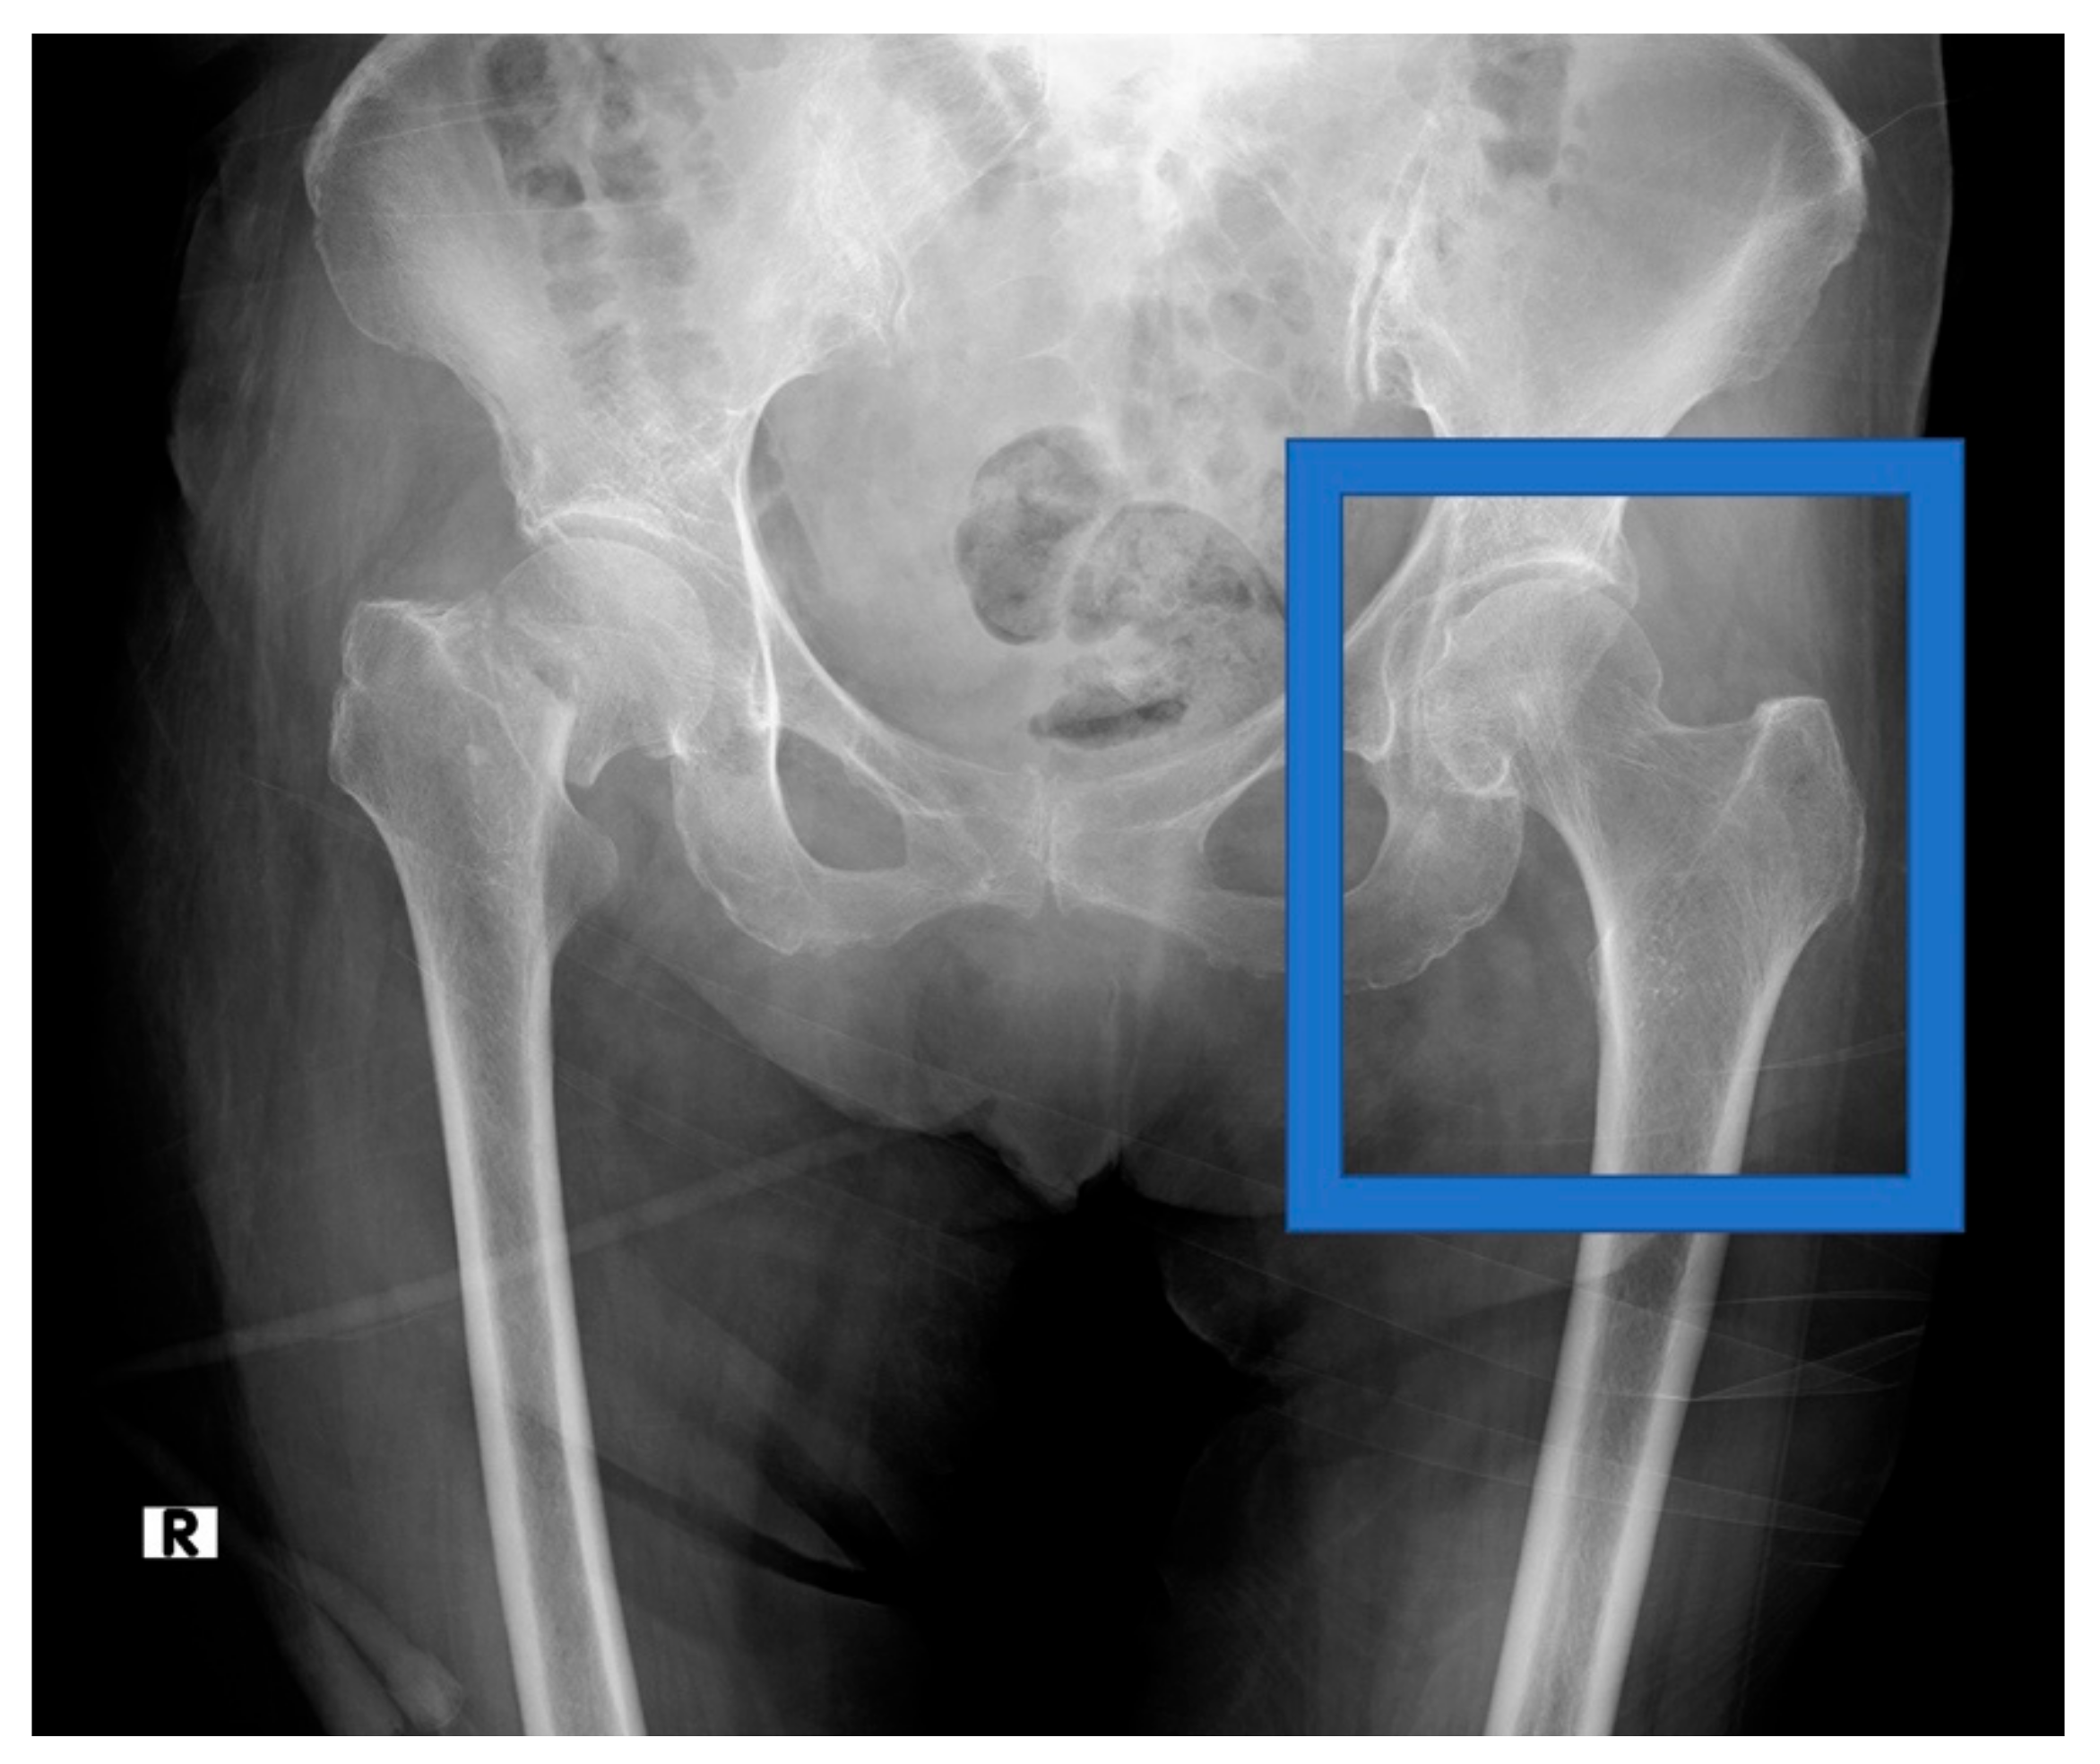

2.2. Data Acquisition

2.3. Data Preprocessing

2.4. Diagnosis of Osteoporosis